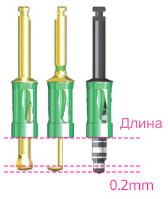

Стоппер-ограничитель

Артикул

Длина (мм)

CDS010

CDS020

CDS030

CDS040

CDS050

CDS060

Артикул

Длина (мм)

Длина (мм)

CDS070

CDS080

CDS090

CDS100

CDS110

CDS120